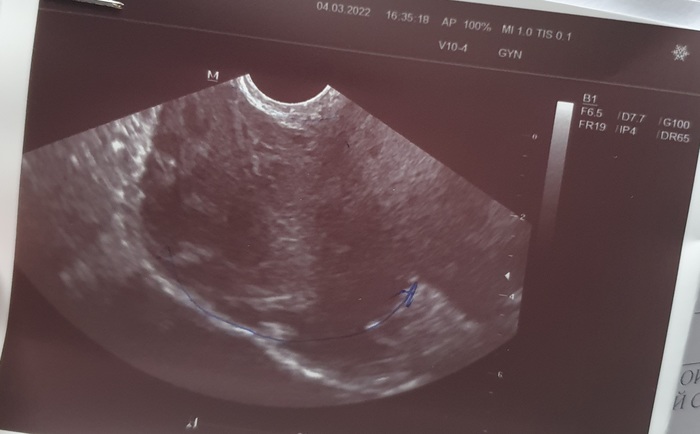

Случилась такая ситуация, по работе отправили пройти диспансеризацию. Случайно обнаружили образование в брюшной полости размером 8.4×10.2×9.5 см (грубо говоря 430+ см в квадрате), на другом узи в тот же день, сказали что размеры 7на7.

Образование большое, мягкое, без жидкости внутри, есть кровоток.

Соседние органы брюшной полости в порядке.

Снимок с узи прилагаю.